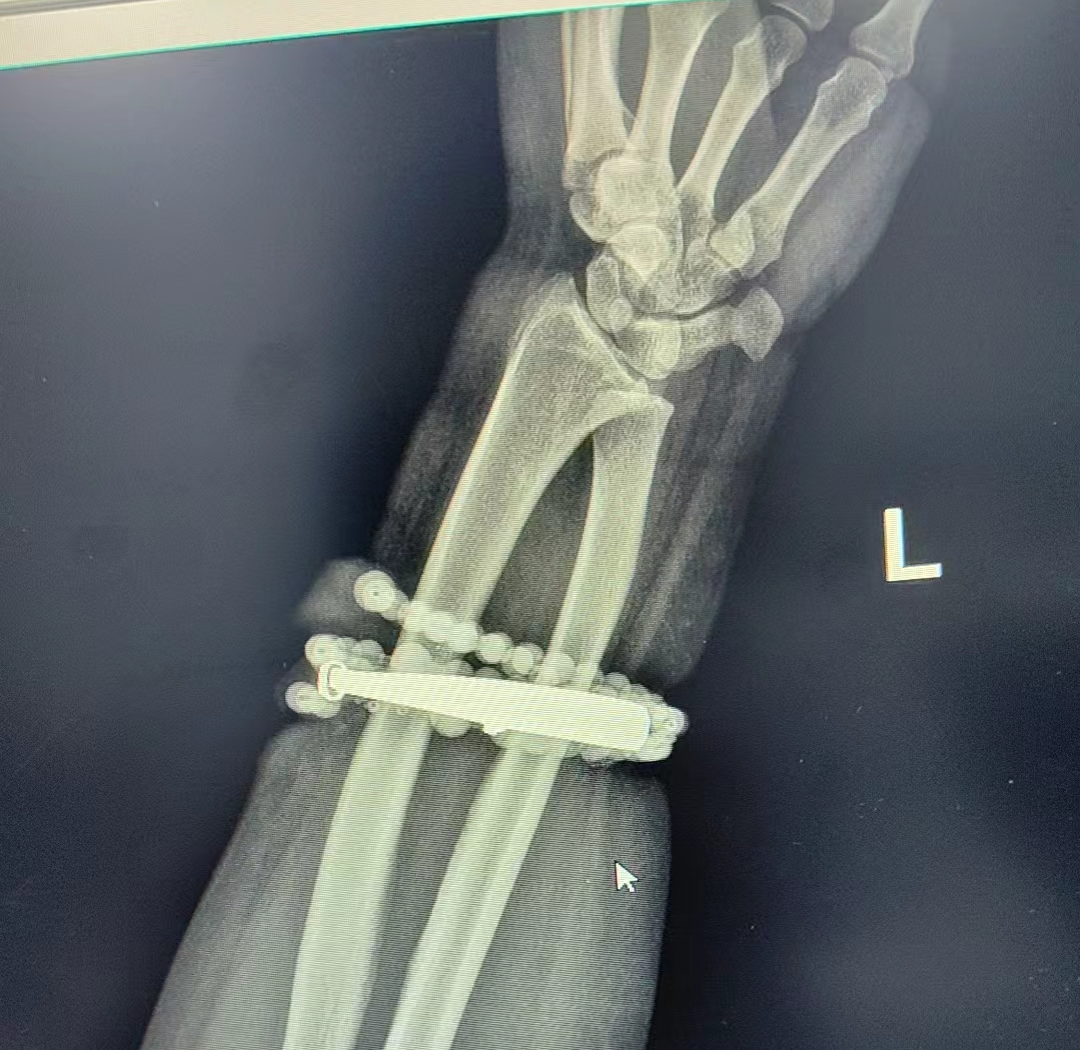

近日,福建省宁德市闽东医院创伤骨科、手显微外科接诊了一位特殊患者,她戴了十年没摘的手镯、串珠竟长进了肉里,还发炎了。

医生介绍,“这是典型的首饰长期压迫、摩擦,加上细菌感染,引发的慢性炎症和肉芽组织增生。”此时,手镯和串珠已经成了一个不断刺激皮肤、污染伤口的“病灶”,如果不尽快手术取出,感染可能进一步扩散,甚至危及生命或影响手臂功能。